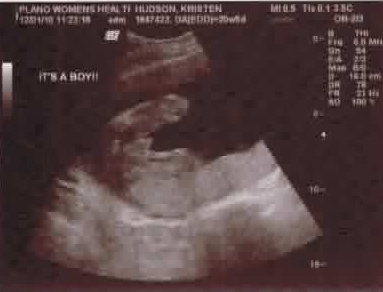

We Are Having a BOY!

It's official finally! We went to the doctor on December 1st and got confirmation that our early-screen doctor was correct in his assessment that we are definitely expecting a boy! We've also chosen Rylan as his first name. It's exciting to start picking out baby boy nursery bedding and everything else blue. We have just 18 weeks left to go. It's hard to believe how quickly this pregnancy is going! Check out the sonogram pics.

Rylan showing off his manhood!

Just for mommy...His sweet little face.